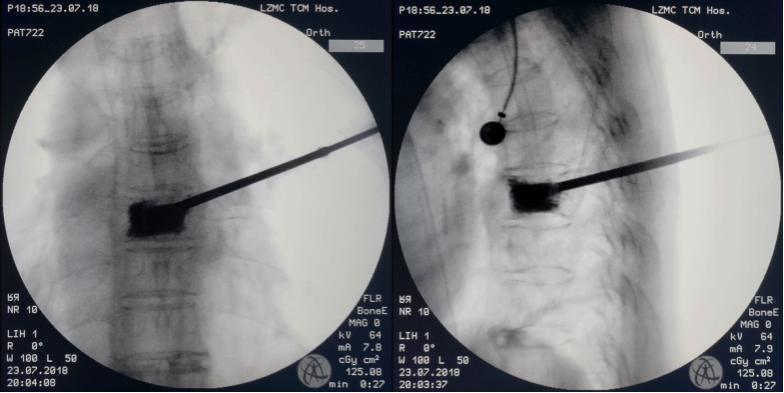

经皮椎体成形(PVP)/经皮椎体后凸成形(PKP)

技术简介:本技术是目前骨质疏松性脊柱压缩性骨折推荐的首选治疗方案。通过一个约3毫米的小孔,在X光机的引导下穿刺骨折椎体,建立工作通道后,操作工具沿中空的工作通道进入椎体,利用球囊扩张恢复椎体高度,灌注骨水泥恢复椎体支撑性及稳定性,即刻恢复脊柱功能,缓解疼痛症状,为患者早期下地活动创造必要条件。

技术特色:PVP/PKP手术创伤小,痛苦轻,时间短(仅半小时左右),手术仅需在穿刺点进行局部麻醉即可完成,出血量仅为几毫升(相当于一次抽血),绝大多数老年患者均可耐受;术后第一天即可起床活动,正常生活,大大缩短了老年患者卧床时间,大大降低卧床并发症发生风险,手术全程在患者清醒的意识状态下,在X光机的监视下完成,相对较安全,手术对患者身体条件要求较低,大部分存在较多内科疾病的患者仍可承受手术,因此目前骨质疏松性脊柱压缩性骨折推荐的首选治疗方案。